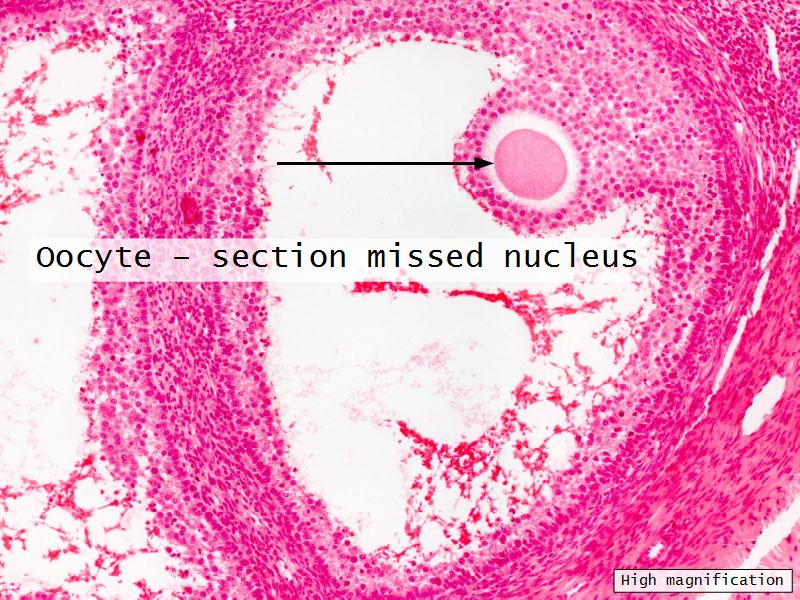

Components of a follicle

- Theca

- externa

- interna

- basal lamina

- Granulosa cells

- Antrum

- Cumulus oophorus >> Corona radiata

- Oocyte